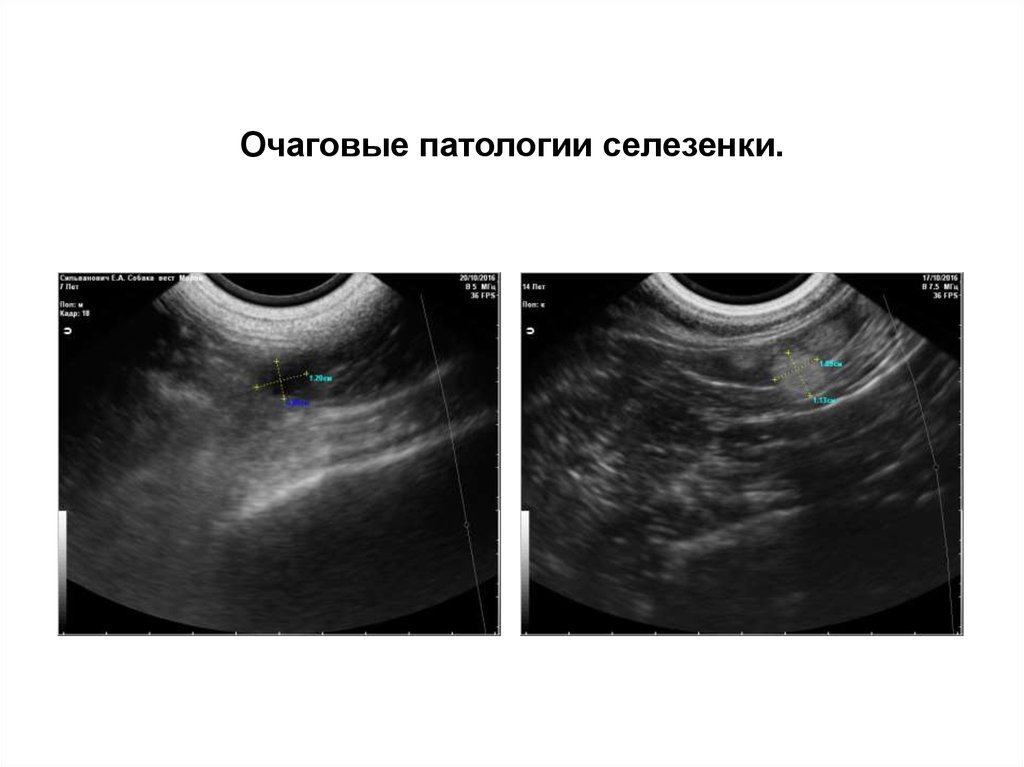

Очаговые патологии селезенки.

1.

2.

3.

4.

Киста селезенки.

Гематома селезенки.

Инфаркт селезенки.

Очаговая неоплазия селезенки.